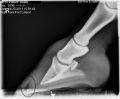

Général > Maladies (700)